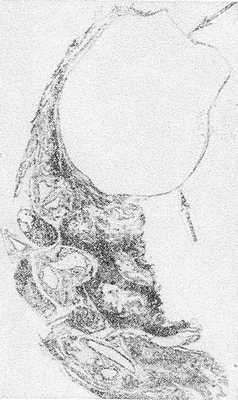

Основанием для такого подхода явилось не только стремление к выполнению функционально-щадящих вмешательств, но и проведенное собственное морфологическое исследование, которое показало, что поражение стенки мочевого пузыря при прорастании колоректальной опухоли в большинстве наблюдений не выходит за пределы видимых границ опухоли. Это позволило нам выполнять субтотальную резекцию мочевого пузыря даже при расположении опухоли вблизи мочепузырного треугольника. Срочное гистологическое исследование линии резекции мочевого пузыря подтверждало отсутствие в ней опухолевых клеток.

Все это позволило нам прийти к заключению, что показания к цистэктомии при прорастании рака толстой кишки в мочевой пузырь зачастую расширяют, основываясь на показаниях к таковой при первичном раке мочевого пузыря, характеризующемся мультифокальным поражением слизистой [9]. При прорастании стенки мочевого пузыря раком толстой кишки иная морфология опухоли определяет другой характер поражения стенки мочевого пузыря.